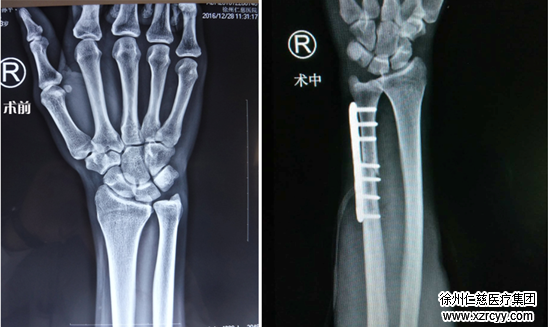

3月8日,专程从北京赶来的刘教授和齐伟亚主任联手,为孙先生做了腕关节镜手术。

结合关节镜探查情况,简单交流后,两位专家决定为孙先生做手术,通过截掉约3.5mm尺骨,扩大两个“轴承”间距离,消除疼痛。